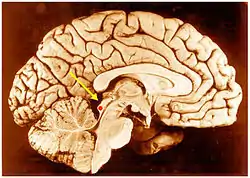

![]() کولیکولوس تحتانی (نقطه قرمز) در مغز انسان، دید چپراستی. | |

![]() مقطع عرضی مغز میانی در سطح کولیکولوسهای تحتانی | |